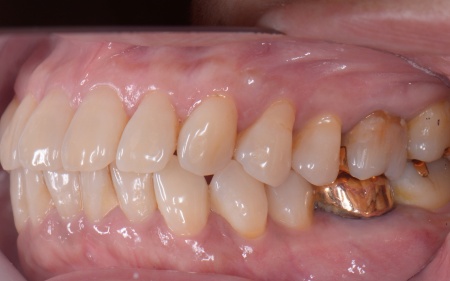

60代女性 重度の歯周病に対して歯周組織再生療法とインプラント治療を施した例

拝見したところ、上下左右の奥歯計8本(第1大臼歯、第2大臼歯)に重度の歯周病が認められました。

特に下の奥歯2本(左右第1大臼歯)は歯を支えている骨が著しく減少して歯が大きく揺れており、治療して温存することは難しい状態でした。

下左右の第1大臼歯を抜歯し、その部位にインプラントを埋め込む手術を行いました。同時に、インプラントの隣にある下の第2大臼歯に対して歯周組織再生療法を施しています。

さらにインプラントの周囲には角化歯肉移植を行いました。これは患者様のお口の中から歯ぐきを採取して移植する方法で、汚れが溜まりにくく清掃しやすい歯ぐきの状態をつくります。

上左右の奥歯についても歯周組織再生療法を行い、歯をできるだけ残せるよう治療を進めました。